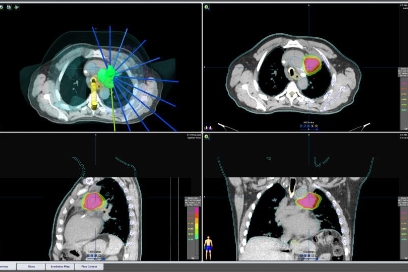

Planeación virtual de tumor en pulmón

Planeación virtual de tumor en pulmón. Físicos médicos y dosimetristas han delimitado los volúmenes blancos y los órganos de riesgo (tejidos sanos circundantes) y calculado la distribución de dosis precisas.

tradiografía de tumor en el pulmón.